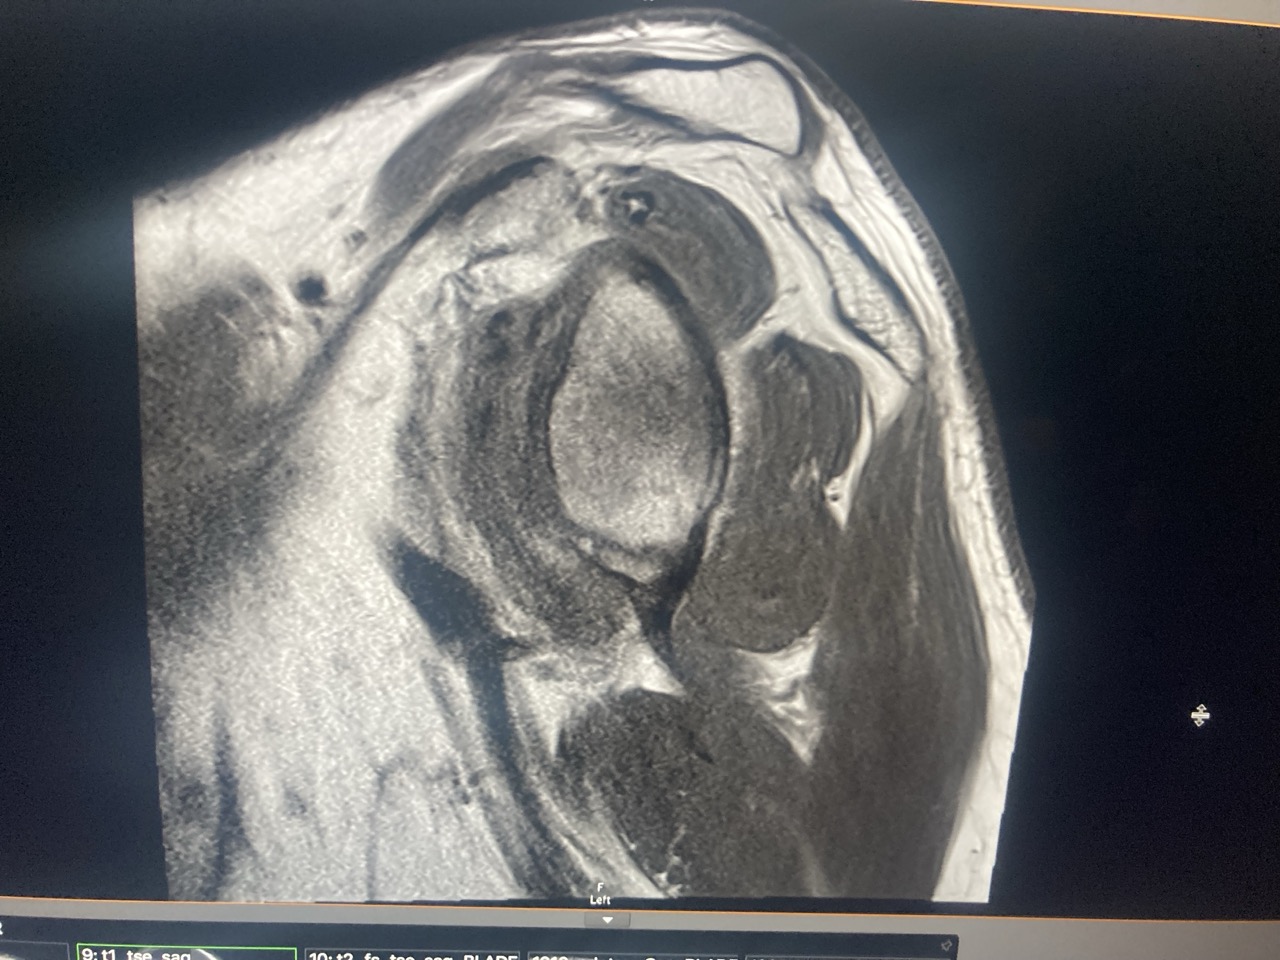

The surgeon was great and was probably more excited about my trip than my shoulder. As was the physio. I think most of their patients my age have a fall and break stuff. Not get hit by a bus while riding a motorbike in Venezuela. His diagnosis. He said the main problem was that I had Post Traumatic Frozen Shoulder. My arm and shoulder had made a pact to never allow anything like that to happen again and had just locked up and it would take 12 to 18 months to regain full movement again. He said I had broken a piece off the end the ball of my arm and a piece of the bottom of the socket that it sits in. His recommendation was that it was healing well and that I didn’t really need surgery. He suggested getting a Hydrodilation injection under a CAT scan and have physiotherapy. And be patient. I did get the injection, and while it didn’t give me much more movement, it did take the pressure off and took the constant pain away which I was grateful for.